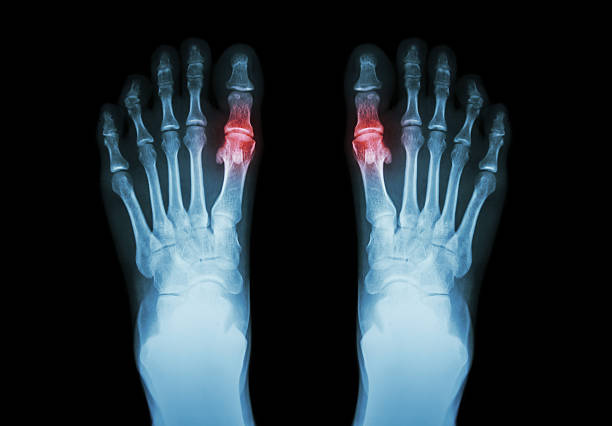

🔬 통풍의 진단 방법

- 혈액 검사 – 혈중 요산 농도를 확인하여 통풍 여부를 판단

- 관절액 검사 – 관절에서 체액을 채취해 요산 결정이 있는지 확인

- X-ray 또는 초음파 – 관절 손상 여부와 요산 결정 침착 확인